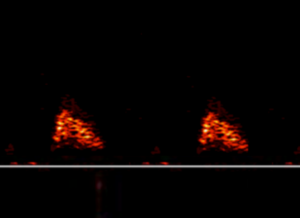

- The waveform should not have spectral dispersion, i.e., it should not be filled in completely with red. If this is seen, it is likely to represent incorrect focus, but also ensure the gain is not too high.

Spectural Dispersion

Inadequate Focus